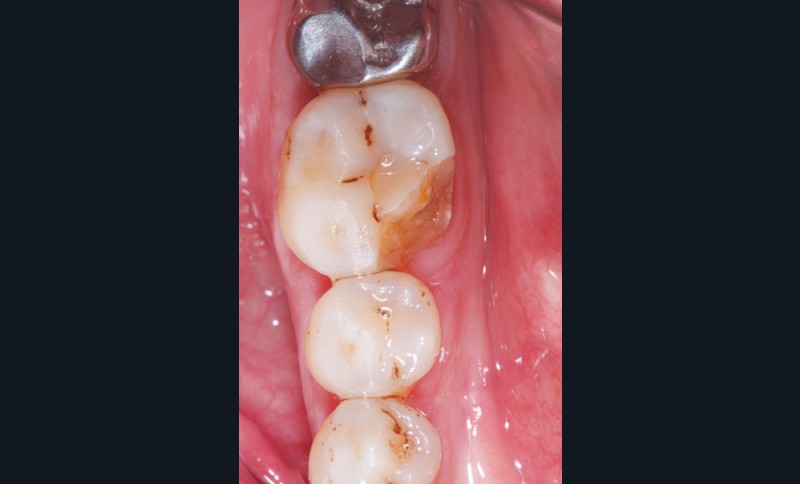

Cette version, quand elle se produit, modifie les espaces interdentaires et complique l’hygiène proximale des patients. Des caries peuvent alors se développer en interproximal sans que cela soit forcément visible à l’examen visuel (fig. 3 et 4). Les radios de type bite-wing (rétro-coronaires) prennent alors tout leur sens (fig. 5 et 6).

La version des dents distales peut aussi avoir des conséquences parodontales désastreuses : sur un parodonte réduit, une hypermobilité peut se développer, une poche parodontale peut aussi apparaître. Chez un patient parodontal, un « effet domino » est possible, des extractions non compensées diminueront donc le pronostic des dents restantes (fig. 7 à 9).